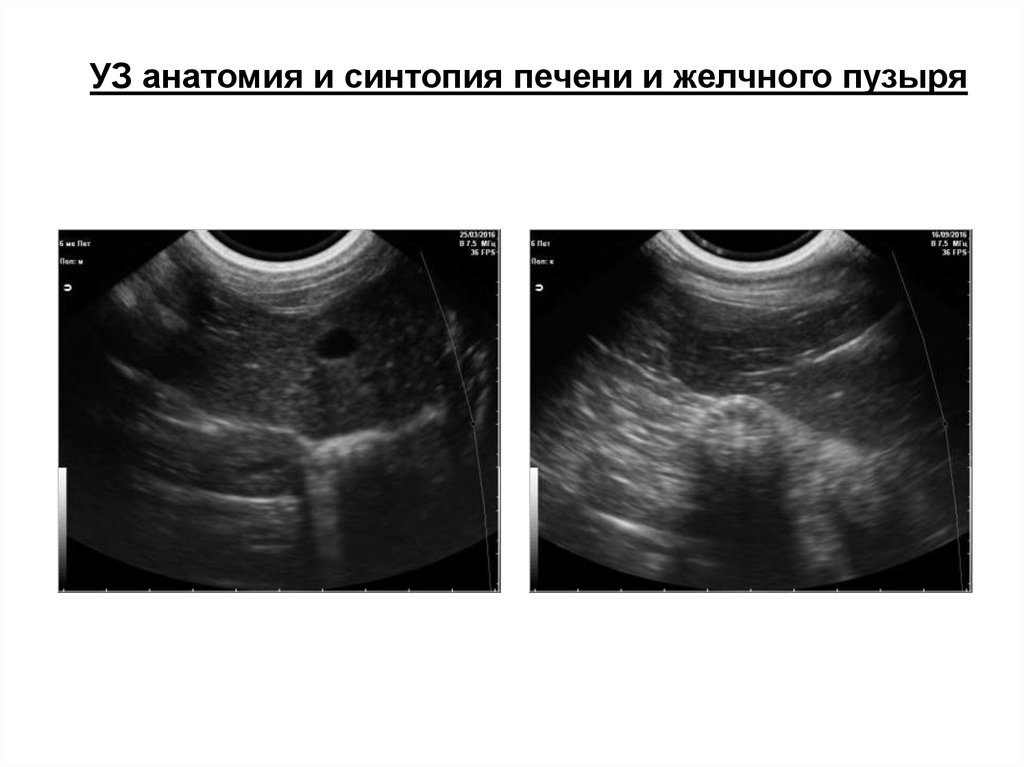

УЗ анатомия и синтопия печени и желчного пузыря